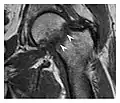

The greater tuberosity of the humerus is also an illustrative location of occult fractures. The osseous injury may follow seizures, glenohumeral dislocation, forced abduction, or direct impaction. They are commonly discovered on MRI in symptomatic patients with suspicion of rotator cuff tear. Coronal images are best suited for detection. They appear as crescentic oblique lines surrounded by a bone marrow edema pattern (Figure 5). The rotator cuff must be inspected since associated ligamentous lesions are common. In the ankle, malleoli and tarsal bones should be checked carefully for any cortical disruptions and radiolucent lines that may reveal a fracture. Awareness of the exact location of the pain will help direct the attention of the interpreter when searching for very subtle signs of fracture (Figure 6).[1]

a

b

Figure 7: Fatigue fracture of the talus in a 25-year-old male basketball player with right hind foot and ankle pain, without history of trauma, and a normal initial radiograph (not shown). (a) One-month followup lateral radiograph shows normal appearance. (b) Sagittal T1-weighted MRI shows an irregular fracture line (arrow) within an ill-defined area of hypointensity corresponding to bone marrow edema.[1]